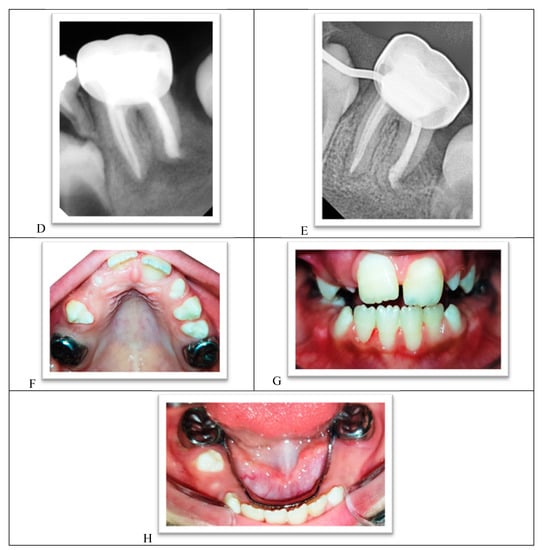

- The procedure involved local anesthesia and rubber dam isolation.

- A pinpoint pulp exposure happened (Figure 6A).

- A coronal pulpotomy was completed by removal of coronal pulp tissue.

- Hemostasis was achieved using 5% sodium hypochlorite and MTA placed as a dressing material over pulp orifices (Figure 6B).

- The tooth was restored like teeth #36 and #46.